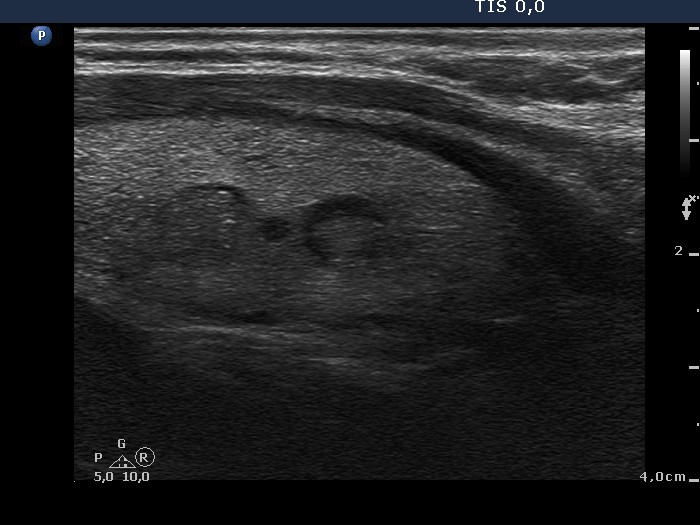

Thyroid cancers - case 670 (ultrasonographic picture 8)

Left lobe, another longitudinal view.